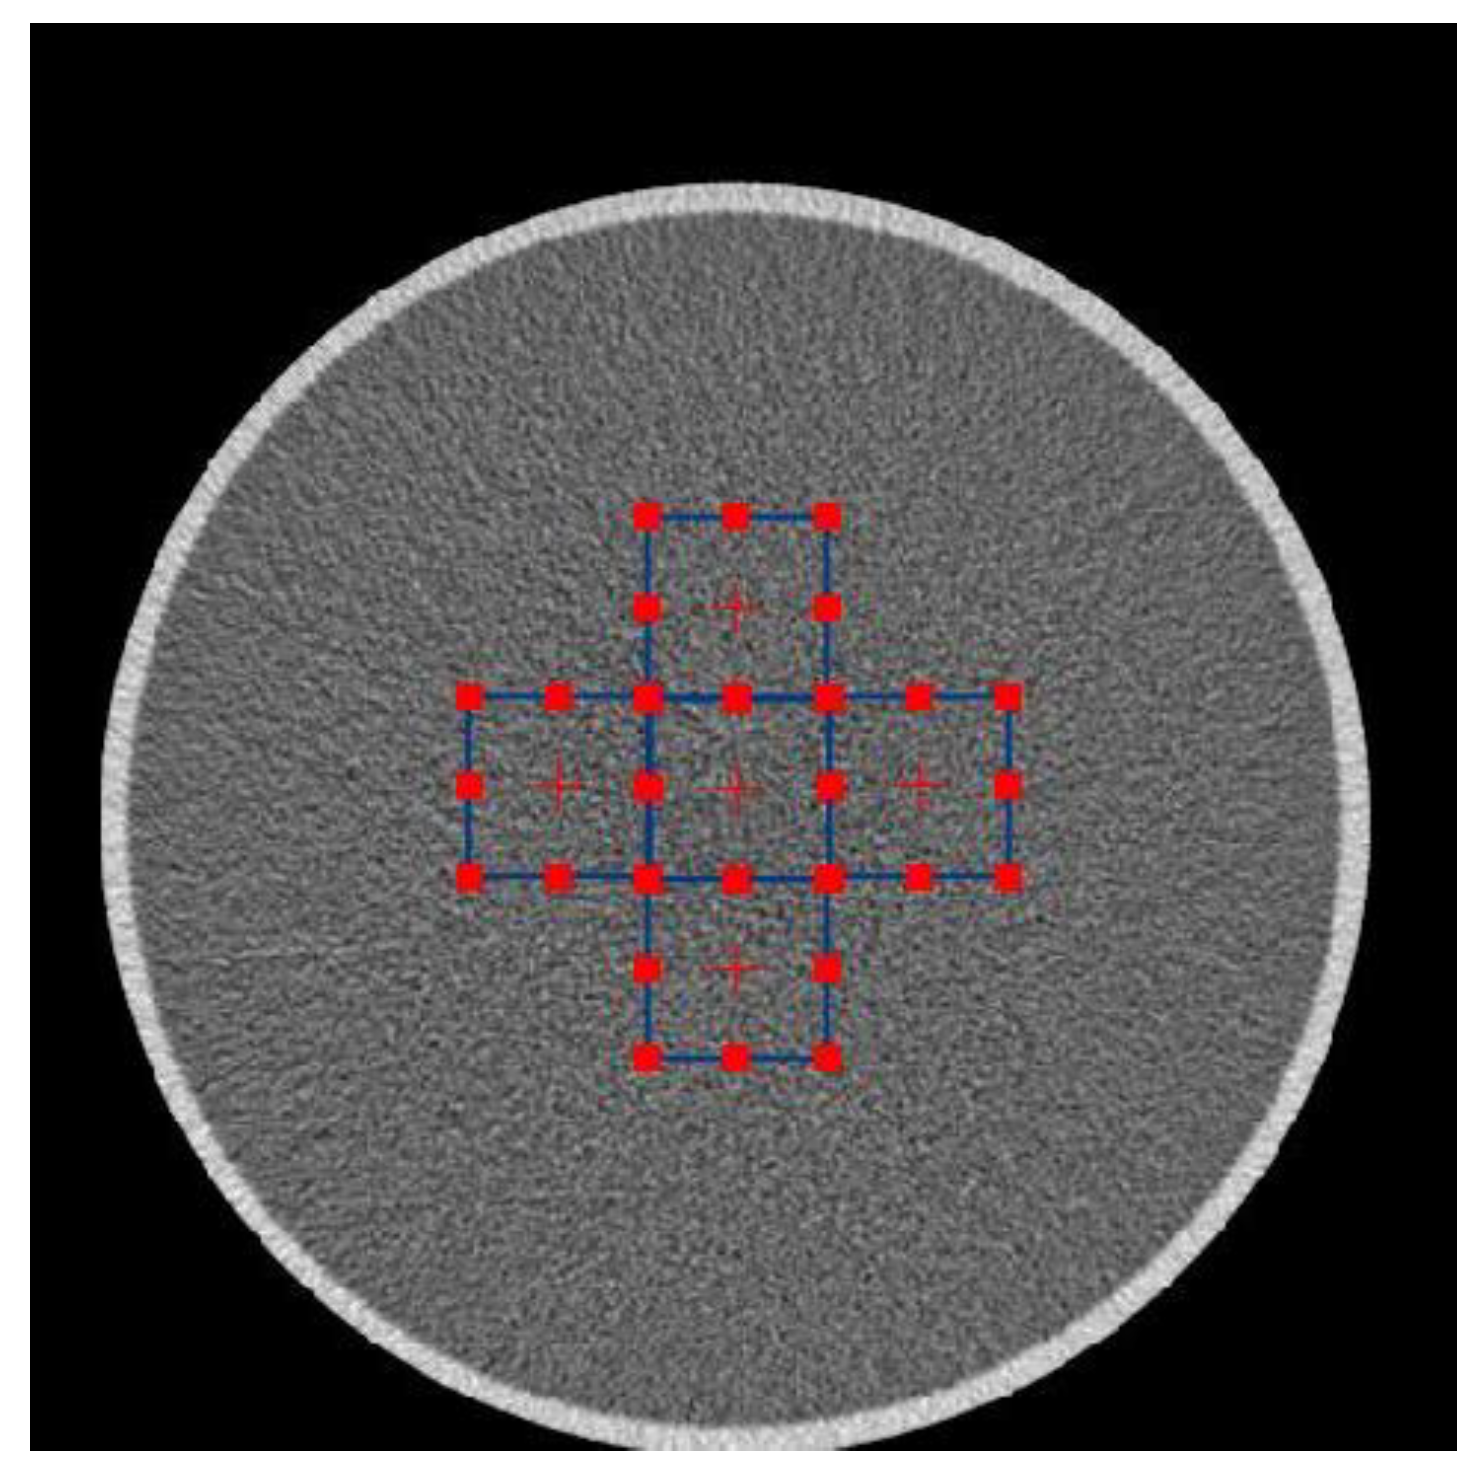

Before filtering an image, we measured NPS using ImQuest (Duke University, Durham, NC, USA) [35] with a total ROI of 5, a size of 64 pixels, and a sampling angle of 10. This was carried out to obtain a description of the noise in the original image before filtering. The ROIs for measuring NPS is shown in Figure 2.

Figure 2.

NPS measurement using 5 regions of interest (ROIs).